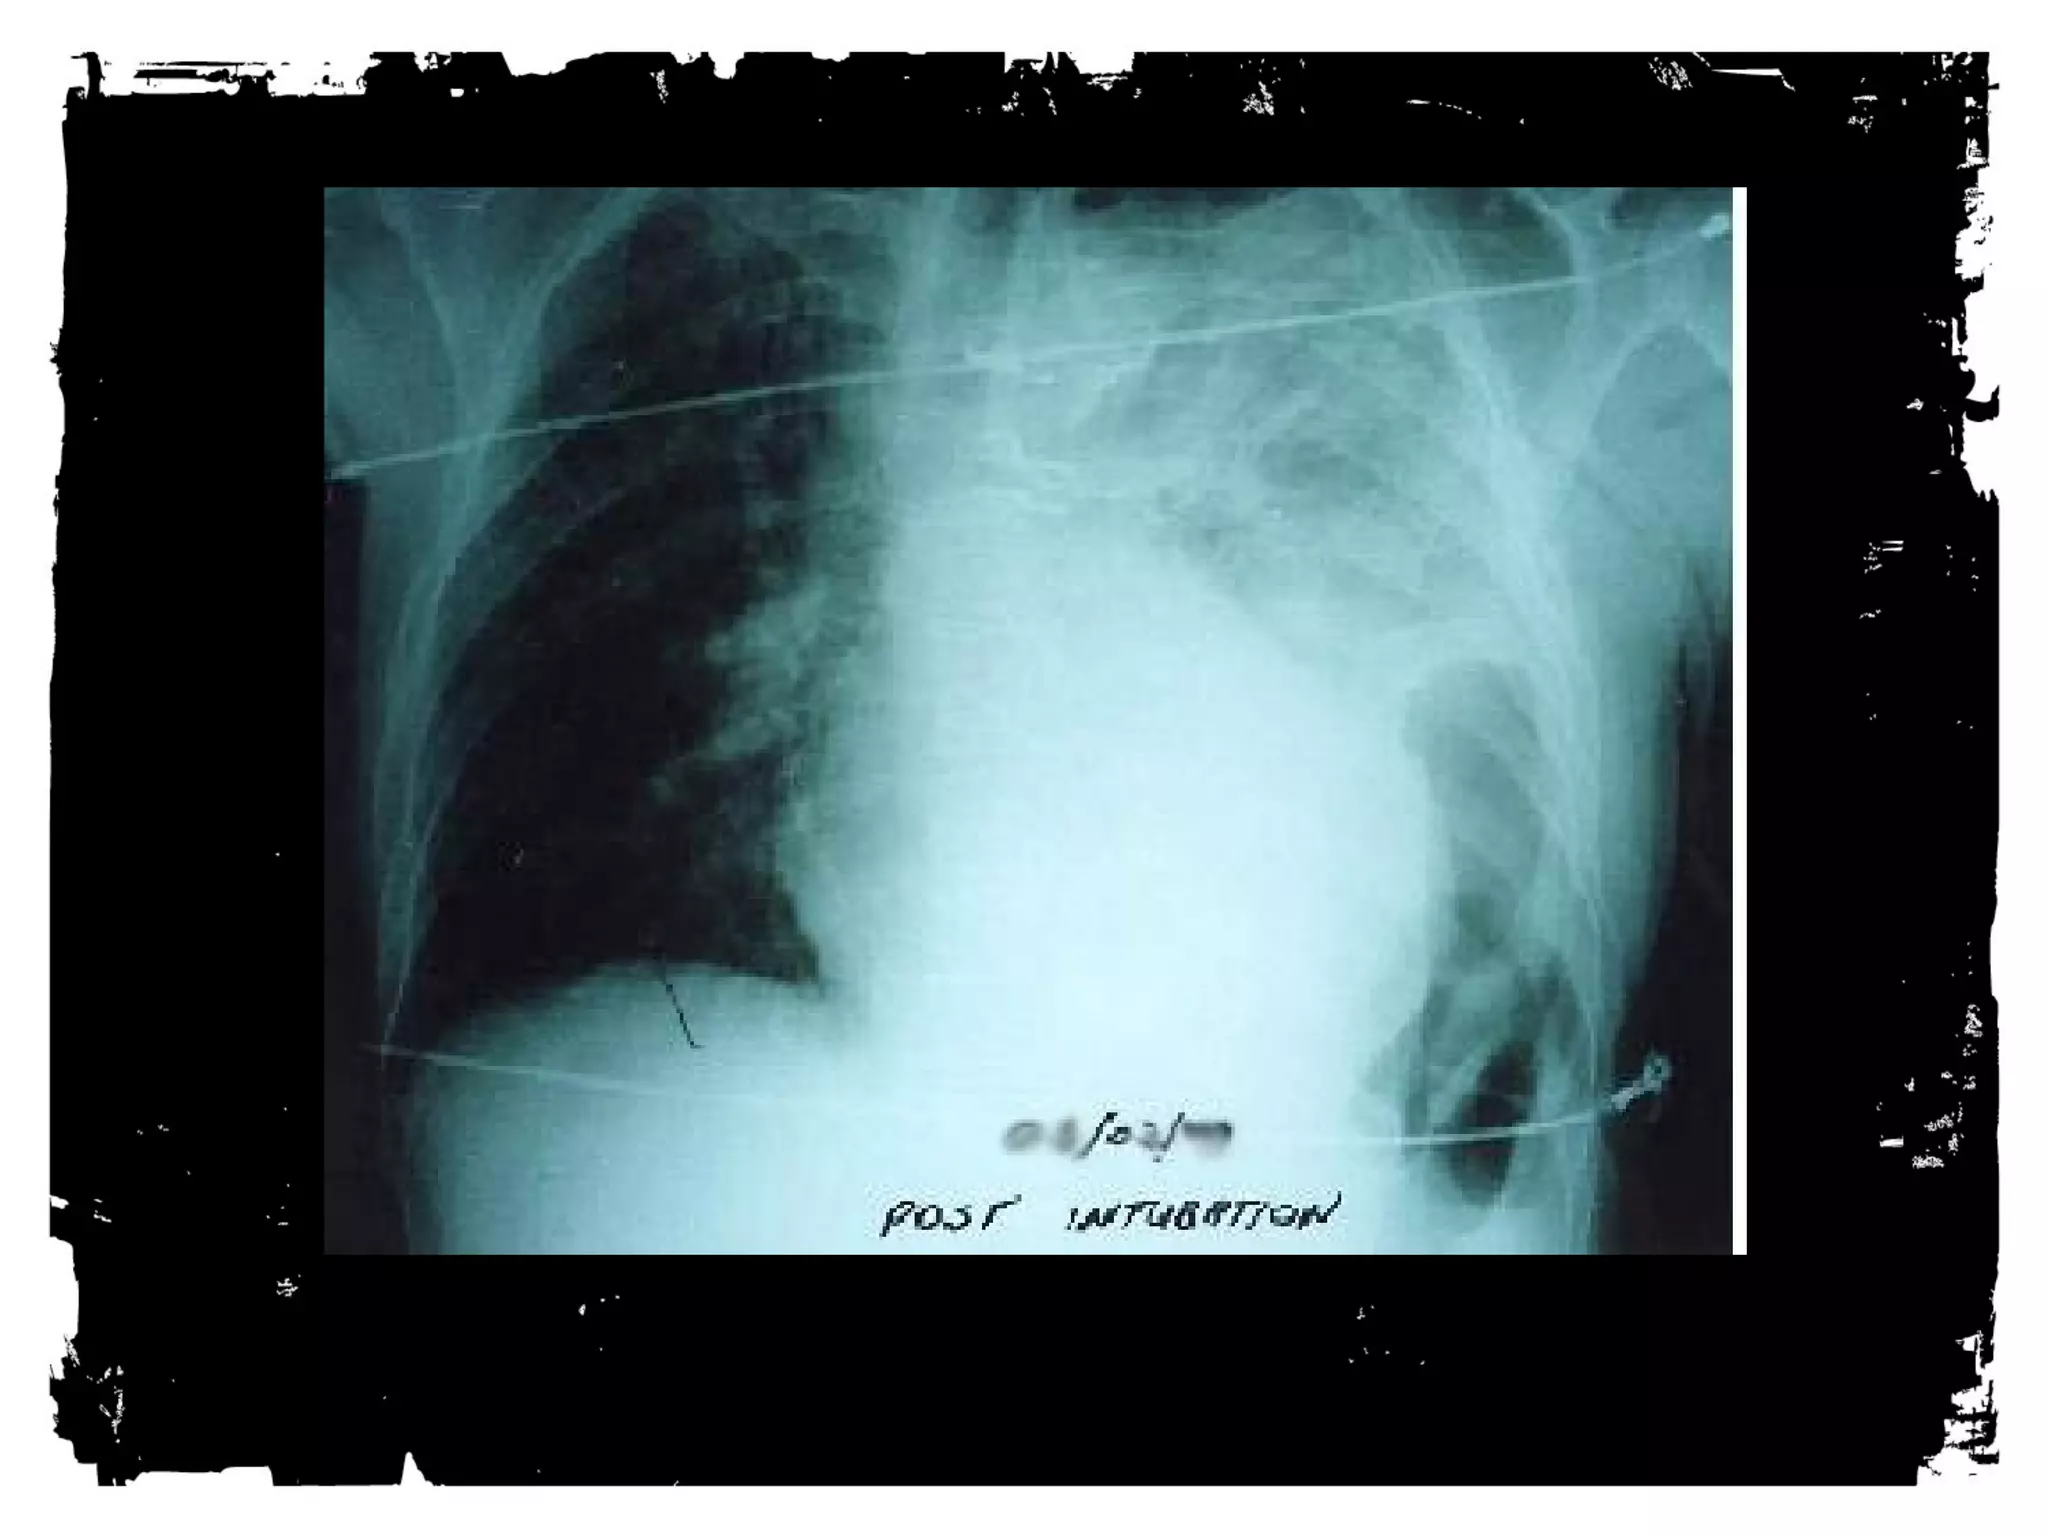

Trauma Chest Radiograph

• Usually AP, often supine,

frequently in poor inspiration.

• So, a challenge to interpret.